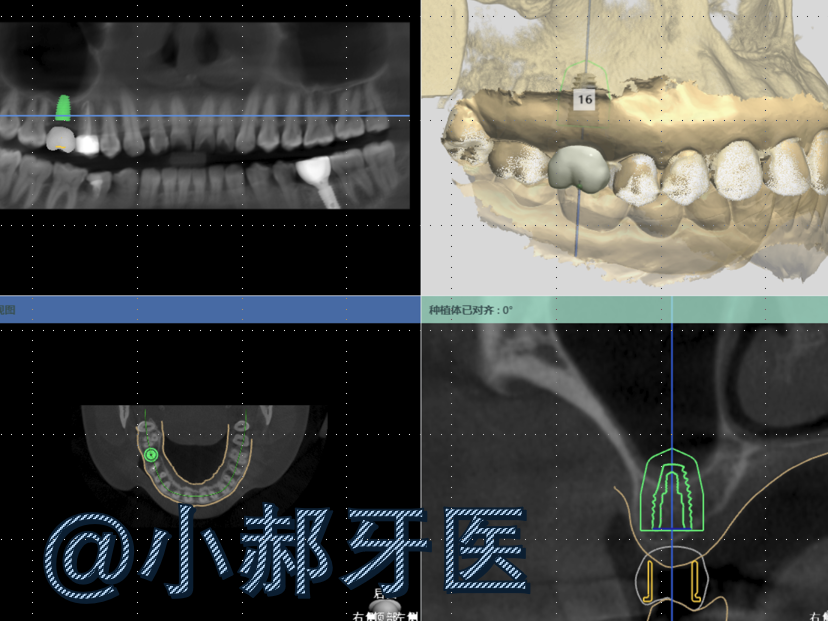

- 导板引导:医生先通过 CT 扫描你的口腔,用电脑 3D 设计出定制导板(类似 “种植导航仪”,通常是塑料或金属做的小模具)。手术时,导板会牢牢贴在你的牙床上,医生跟着导板的 “指引”,精准把种植体放进预先规划的位置 —— 就像 “按图纸搭积木”,不用凭手感 “猜”!

最近的病例给大家看一下。